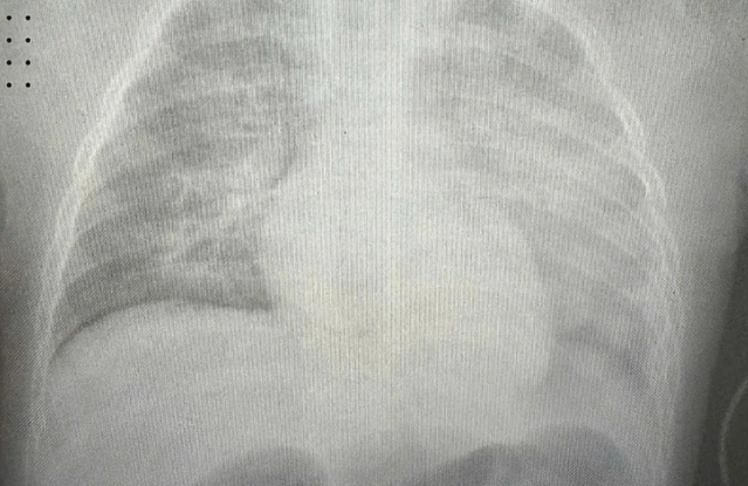

Bác sĩ nhận định trẻ mắc biến chứng nặng do sởi, nguy cơ tử vong rất cao. Sau 6 tiếng nhập viện, bệnh tiến triển thành hội chứng ARDS (hội chứng suy hô hấp cấp tính), xét nghiệm khí máu rất xấu, kết quả chụp X-quang phổi trắng xóa.

Bé được hồi sức chống sốc, thở máy, sử dụng kháng sinh tĩnh mạch. Những ngày đầu, trẻ phải thở máy thông số cao, dùng hai thuốc vận mạch liều cao phối hợp mới giữ được huyết áp đạt đích. Ngoài ra còn là vấn đề tăng áp phổi, suy gan, rối loạn đông máu, cân bằng nước và điện giải.